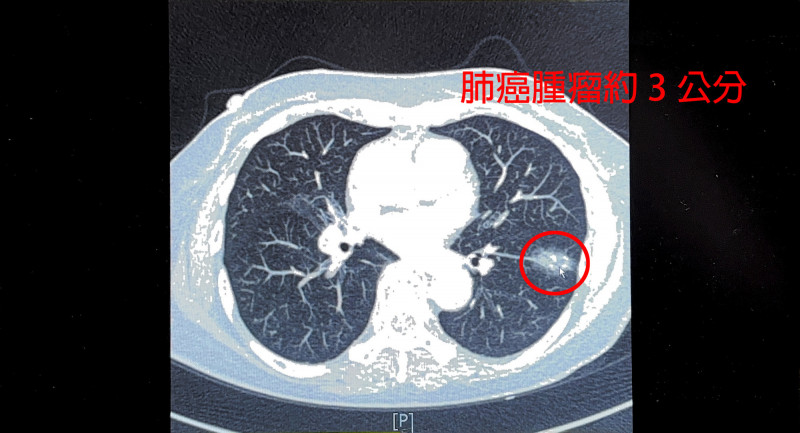

〔記者廖雪茹/新竹報導〕一位75歲婦人不菸不酒,今年安排健檢LDCT肺癌篩檢,意外發現左下肺葉有一顆接近3公分的惡性腫瘤,而求診中國醫藥大學新竹附設醫院胸腔外科醫師謝義山;在執行達文西手術前,醫師發現患者曾在10多年前罹患肺結核,造成肺部淋巴像石頭一樣硬,並與血管沾黏,歷經4個小時手術,病患住院3天後出院,恢復狀況良好,目前持續追蹤。

謝義山表示,他在為這名婦人執行達文西肺葉切除手術前,發現患者因為肺結核感染的病史,造成縱膈淋巴結跟石頭一樣硬,與血管沾黏嚴重,一旦手術時分破血管,瞬間可能就是數千甚至上萬cc的大流血。幸好透過達文西手術,在機器手臂輔助下進行血管分離結紮,左下肺葉有3條主要肺動脈分離後,雖然兩條分支分破流血,但順利止住流血,最後只有200cc的出血量。開完刀建議要努力深呼吸、咳痰,盡早下床活動, 休息兩周即可以從事輕便的工作,建議2-3個月後再從事粗重工作或是運動。